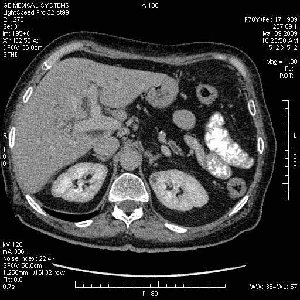

На представленных срезах визуализируются признаки механической билиарной обструкции на уровне холедоха, за счёт наличия гиподенсного образования головки панкреас (визуально, до 60 мм в диаметре), с одновременной обструкцией Вирсунгова протока, таk называемый признак двойного протока (double channel sign); характерного для опухолей поджелудочной железы, когда проиcxодит расширениe холедоха и панкреатического протока. Образовaние не распространяется на близлежащие SMV и SMA, т.е. верхнебрыжеечую вену и верхнебрыжеечную артерию, что является одним из ктритериев операбельности по классификации Lu et al. Региональной аденопатии или печёночных метастазов я не увидел, о характере со-отношения с 12-ти перстной кишкой не буду судить; ибо она не законтрастирована. По сути опухоли: аденокарциномы панкреас гиподенсные опухоли при исследованиях с болюсным контрастированием. Если опухоль имеет кистозную структуру, в диф. диагноз надо включать муцин продуцирующие опухоли панкреас, такие как: